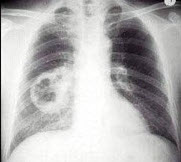

3、单项选择题

男,74岁,咳嗽,咳痰1月余,咯血丝痰1周伴胸痛,胸片如图,最可能的诊断为()

A.右上肺浸润型肺结核

B.右上肺不张

C.右侧中央型肺癌并右上肺不张

D.右侧包裹性积液

E.右肺上沟瘤